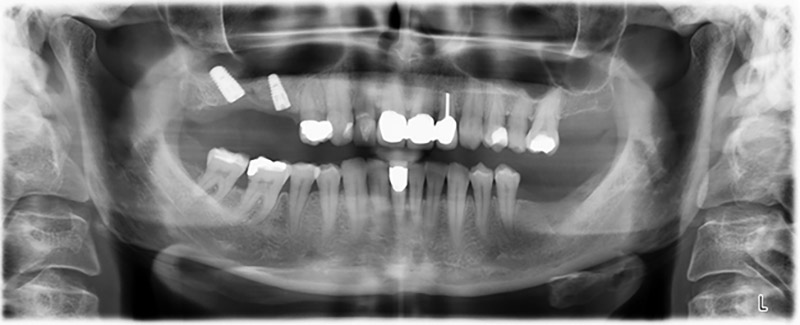

Abb. 20: Orthopantomogramm nach Behandlung